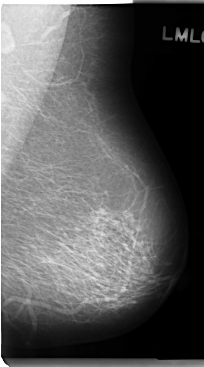

C_0285_1.LEFT_MLO

LEFT_MLO LINES 4760 PIXELS_PER_LINE 2640 BITS_PER_PIXEL 12 RESOLUTION 50 NON_OVERLAY